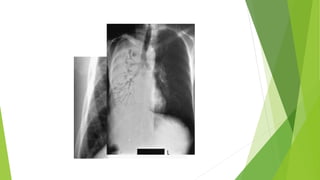

Broncograma Aéreo:  Ca.Bronquioloalveolar

Broncograma Aéreo:  Losinfiltrados pulmonares parcheados periféricos o la enfermedad intersticial generalmente no causan una opacidad suficiente para producir broncograma aéreo.  Las entidades que cursan con hiperinsuflación pulmonar no causan broncograma aéreo(asma, fibrosis intersticial, cáncer).

Broncograma Aereo:  Lamorfología del broncograma aéreo nos puede dar algunas referencias importantes para el diagnóstico diferencial entre las neumonías y atelectasias  En el caso de neumonías la arborización bronquial corresponderá al patrón normal radiológico o TC.  En el caso de existir atelectasia, los bronquios se justarán adoptando una disposición “paralela y comprimida”, que indicará una pérdida de volumen del territorio en que se ha producido